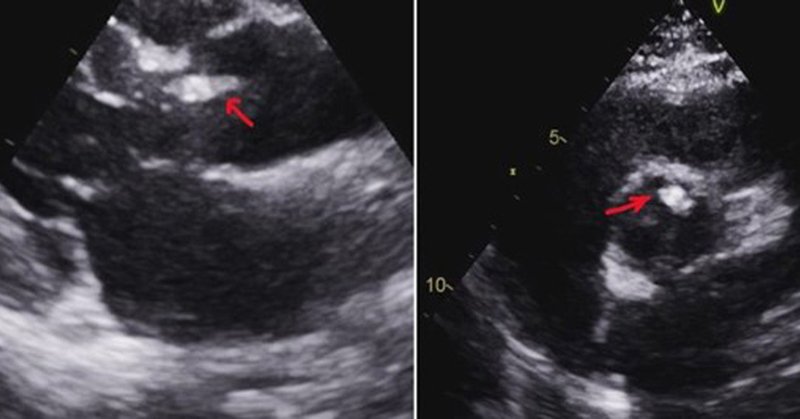

Thread 🧵 1/ “Vegetation Biopsy”—are we entering a new era of precision medicine in infective endocarditis? Is empiric therapy for culture-negative IE becoming unacceptable with new diagnostic tools emerging? https://t.co/1ITaXt4nJu